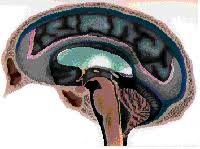

Foto que demuestra las estructuras anatómicas implicadas en la producción y flujo del líquido cerebroespinal con el sistema ventricular, el cerebro y la médula espinal, y finalmente la absorción en la circulación sanguínea. Usted también verá que la diferencia entre un cerebelo "normal" y el cerebelo de un paciente de ACM con las amígdalas cerebelosas que resaltan con foramen magnum.